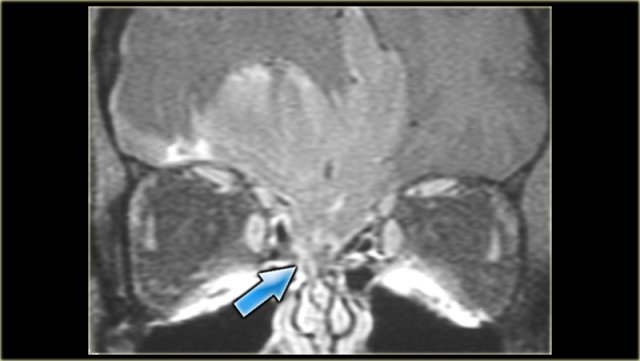

On the left images of a 64-yrs-old, immuno-competent patient, who had a follow-up scan for left-sided vestibular neuroma.

On the image on the left hypointense tissue is seen in the pterygo-palatine fossa and videan canal (yellow arrow).

On the image on the right, which is more cranial, there is hypointense tissue in the pterygo-maxillary fissure and pterygo-palatine fossa.

Continue with the contrast-enhanced T1W-image.

Sinonasal carcinoma Sinonasal carcinoma

There is solid enhancement of the abnormality.

The differential diagnosis again consists of 2 catagories: neoplasm and chronic invasive fungal infection.

In an immuno-competent patient, a neoplasm is much more likely.

Continue with the CT-images.